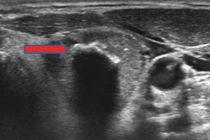

Ung thư tuyến giáp là một trong những bệnh thường gặp ở vùng đầu, mặt, cổ ở cả nam và nữ giới, bệnh thường không có dấu hiệu rõ ràng nên âm thầm di căn đến nhiều bộ phận khác, khi phát hiện bệnh đã ở giai đoạn muộn.